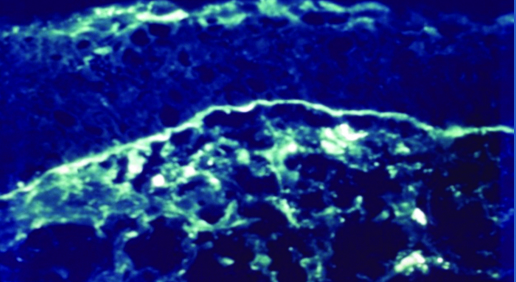

Estudios más complejos de laboratorio como la inmunohistoquímica (Fig. 17) sobre tejido conjuntival obtenido por biopsia permite el diagnóstico de certeza del penfigoide ocular cicatrizal al identificar depósitos de IgG, IgM y Complemento 3 en membrana basal.

Figura 17: Inmunohistoquímica